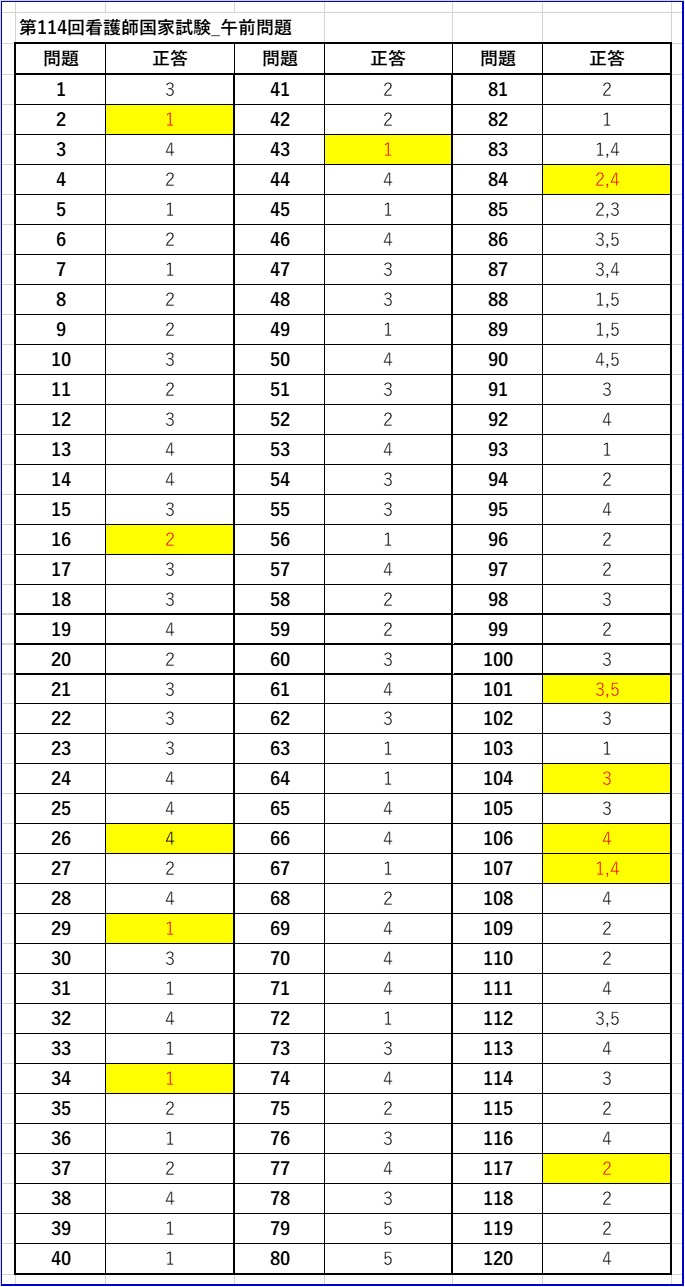

71ASbdgC9mL.jpg。第114回看護師国家試験 午前必修問題 | 一般財団法人厚生労働。2ページ目:第114回 看護師国家試験 解答速報 ただいま公開中。看護師国家試験2024年に使用していた国家試験対策のものです。・でた問 ¥1681・ここだけおぼける ¥1500+税・ゴロ勉 ¥1500+税・プチナース看護師国家試験過去問題集 ¥5940・クエスチョンバンク必修問題集 ¥3190・クエスチョンバンク国家試験問題解説 ¥6490・1番最新の国家試験で実際に私が解いた問題と添削した解答付きのもの(113回の国試問題)・その他問題集10冊プラスプリントは自分が模試を受けた解説に貰ったり、学校の授業で使用をしたものなので非売品ですが、解説がしっかり載っており非常に分かりやすく役に立ちました。これだけついてこの値段はかなりお得です。送料はこちらもちで配送はクロネコヤマトでします。。必修問題 – 114回看護師国家試験 – 心電図波形 心室脈拍。これさえやっていれば東進などの10万以上する高い講義に通っている方もいましたが、そういうものにお金を払わなくてもこれだけで私は250点以上は取れました。AGOS TOEFL 教材 2017年 CD8枚付き。メキメキ力がつく受験英語の集中講義。使用していたので安くしています。24年度卒 歯科衛生士教科書。KORON 警察 昇任試験 2024 1〜10。4月からは仕事で忙しくなるので3月中に購入いただけたらすぐにお送りできます。東進教材漢文。【25冊】ひろゆき 西村博之 全巻帯付き 2ちゃんねる 論破王 成田悠輔 ja。ご検討宜しくお願いします。希学園基礎計算問題集&難問計算問題集